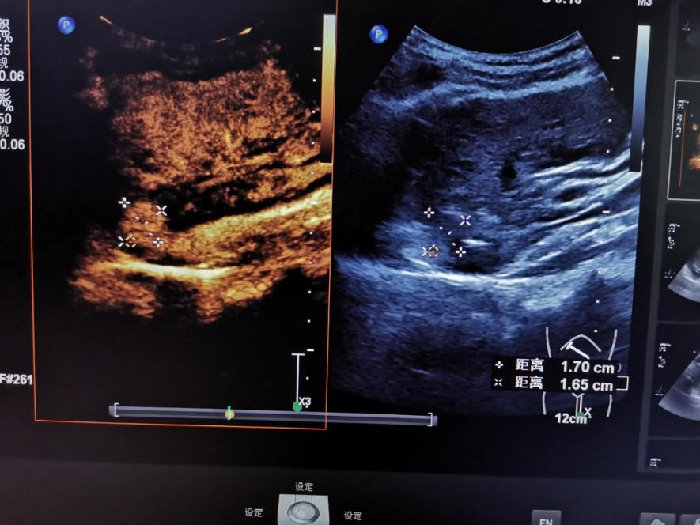

针尖上的医术—陕中附院超声诊断科成功完成一例高难度肝癌消融术